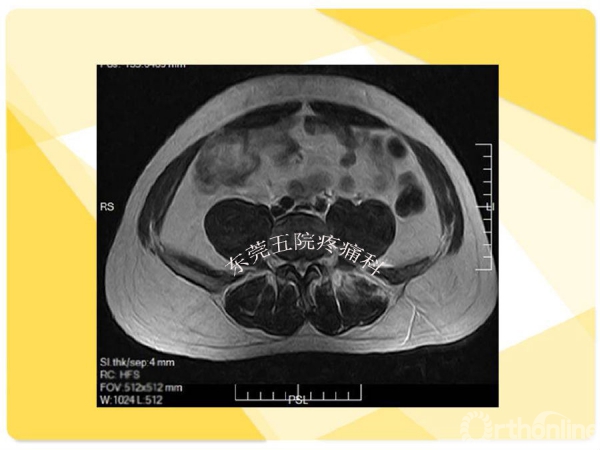

如何在椎间孔镜术前有效预防并发症的发生?如果不幸发生了该如何快速准确地处理?广东省东莞市第五人民医院疼痛科康健主任医师为大家分享了他的经验——